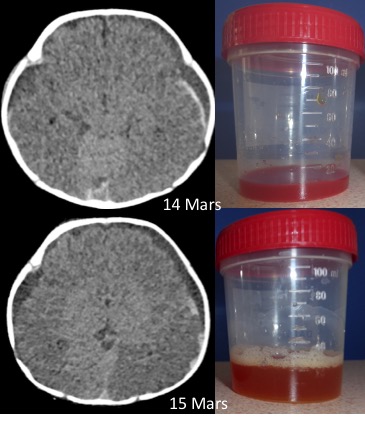

d’intervalle ; on note que le liquide s’éclaircit, que la densité au scanner

diminue, ce qui traduit sa dilution par le LCS.

l’aspect du liquide sous-dural ponctionné ou drainé est typique : il s’agit dès le départ de sang mélangé de liquide cérébrospinal, qui se dilue progressivement (cf. ci-contre) et finit par être limpide.